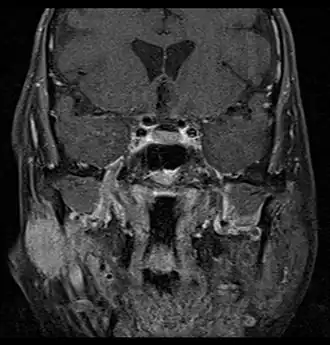

MRI or CT Scan: These tests can confirm the presence of a tumour. An MRI or CT Scan can also show whether metastasis has occurred.[4]